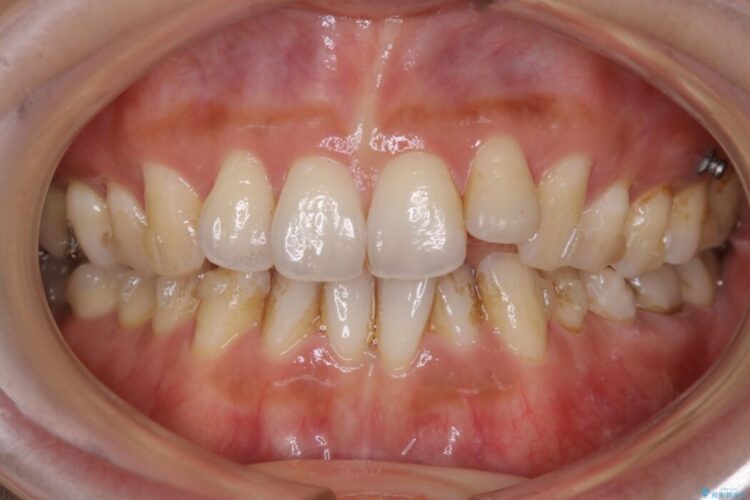

ガタガタした歯列の見栄えが悪く歯磨きがしづらいとのことで来院されました。

笑った時の歯の見え方が改善され患者様にご満足いただけました。